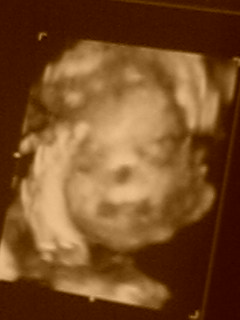

病院行ってエコー見てきました(●´ω`人)しかも4Dで顔まで見れちゃうんです!

男の子だそうですよ!!長男Getです!ヾ(゜∀゜)ノわぁい!

生まれてみたら実は女の子だった…って事も無くは無いみたいですが、9割男の子らしぃです。

その時の映像をVHSに録画してもらいました。一生の記念ですねぇ、誰もVHS再生出来る物持ってないけど(笑)大事にします

この写真…子宮の壁に顔埋まってるから分かりにくいけどー…ってお医者さんが言ってました。ほんとわかりにくいです;;;まだカワイィとは素直に思えないなぁ(´ω`)言っちゃ悪いけどやっぱエコー写真て不気味だね…

性別報告したら、親にも親戚にも学さんの店のスタッフさんにも「やっぱりねぇ」って言われたのは何故なんでしょう(^^;)男の子連れて歩いてそーなイメージなのかな?うーん、顔つきがキツくなったから…??